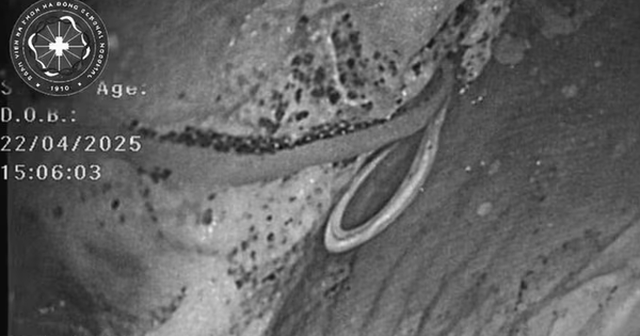

Trong quá trình nội soi đại tràng, bác sĩ chuyên khoa II Nguyễn Hợp phụ trách Trung tâm Nội soi bất ngờ phát hiện một hình ảnh bất thường: một ký sinh trùng dạng sợi trắng, dài, đang cuộn trong lòng ruột. Đây được xác định là nguyên nhân trực tiếp gây ra các triệu chứng kéo dài ở bệnh nhân.

Hình ảnh kết quả nội soi đại tràng của bệnh nhân. Ảnh: BVCC.